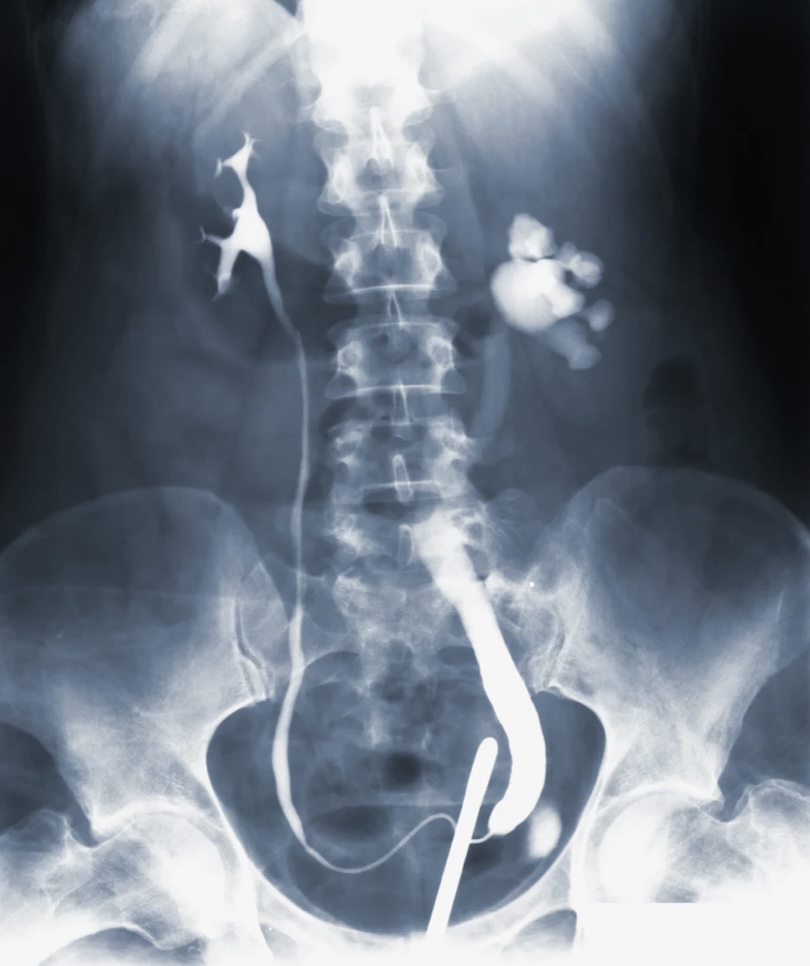

일반적으로는 신장 대체 요법인 투석이나 신장이식이 주로 사용됩니다.

투석은 혈액을 청정화하여 독소와 노폐물을 제거하는 과정으로, 혈액을 체외로 배출하고 정화한 후 다시 체내로 주입합니다.